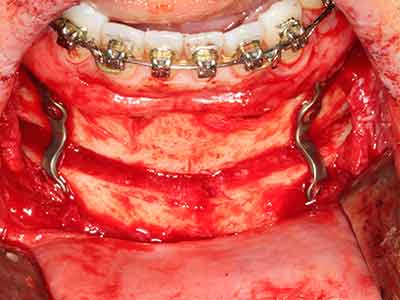

As shown in the past, basically any bone surgery procedure represents a possible indication for piezosurgery. Thus preparation of the mobile segment in distraction osteogenesis (Fig. 23-25) and sandwich osteotomy uses special attachments without endangering the blood supply to the crestal section, which is essential for the success of both techniques (Gonzalez-Garcia, Diniz-Freitas et al. 2008).

Purely orthodontic indications include orthognathic surgery, genioplasty (Fig. 27-30) and orbital decompression in patients with advanced endocrine orbitopathy as a result of Basedow’s disease (Ponto, Zwiener et al. 2014). Piezo devices are also used in maxillofacial surgery and to remove tumours at the base of the skull in various hospitals.